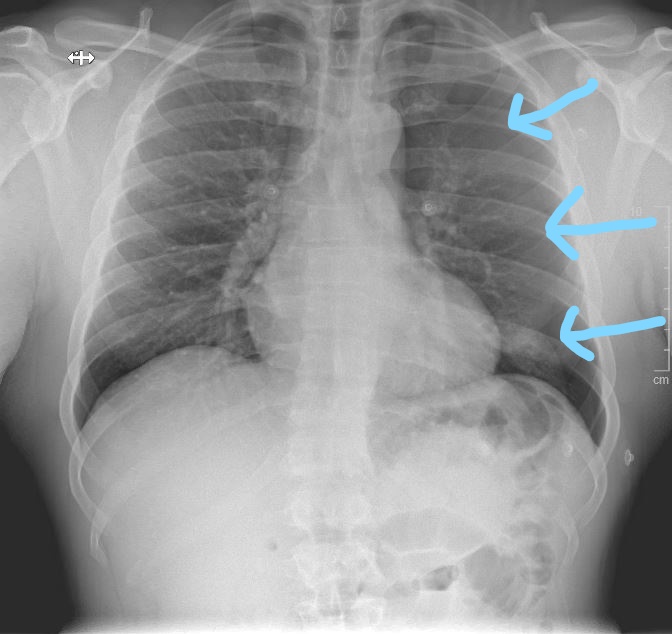

CXR:

CXR interp: Moderate sized L sided pneumothorax (blue arrows show pleural line)